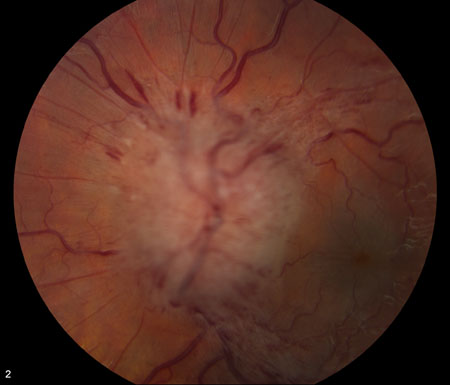

Hipertensão intracraniana idiopática

Estágio 4 da escala de Frisén

Do acervo pessoal do Dr. M. Wall; usado com permissão